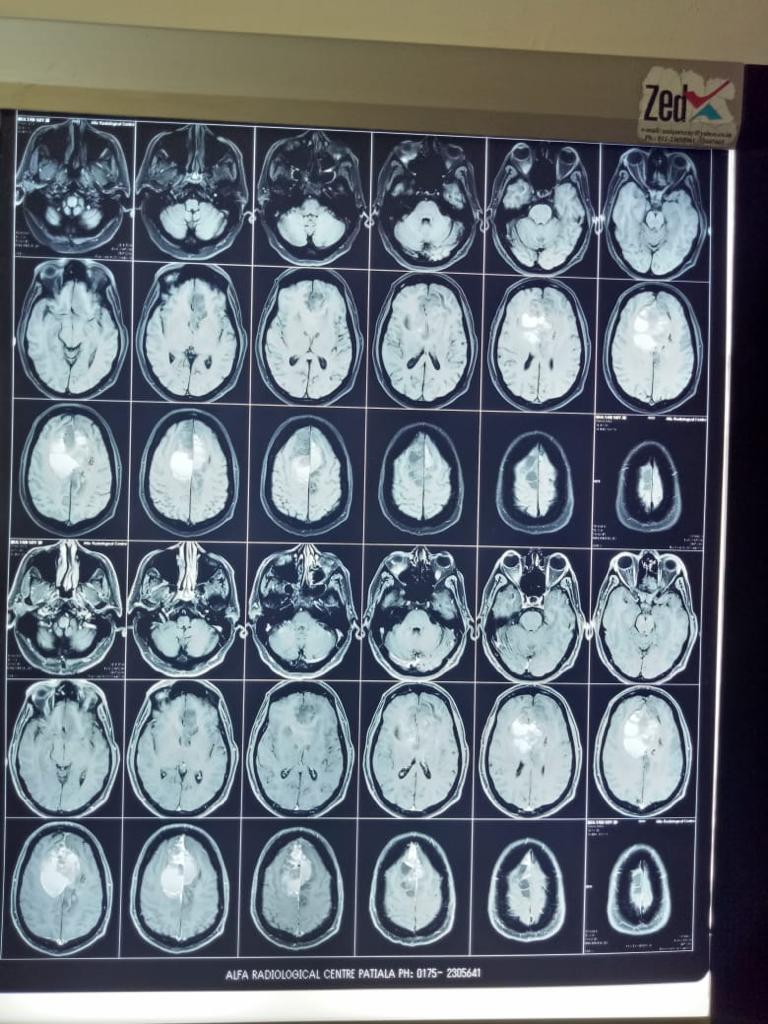

Cases